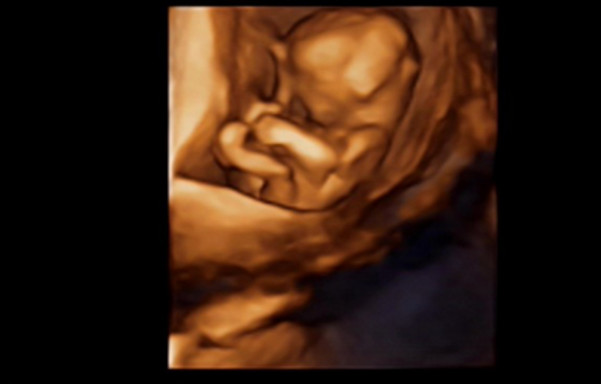

27岁的曹女士,已经怀孕六个月了。三天前,“孕味十足”的她,在丈夫的陪同下来到医院,准备进行提前预约好的四维彩超检查。但是万万没想到,检查结果让她的心情一下跌入低谷!通过影像显示,胎儿嘴唇中间竟然有一指宽的裂痕。经过医生再次仔细确认,腹中的胎儿确实患有唇腭裂,也就是“兔唇儿”。

唇腭裂患儿,是由于牙槽突间骨策划的缺失,导致上颌牙弓的完整性丧失,鼻基底部塌陷,牙槽突裂隙部恒尖牙萌出受阻。胎儿出生以后,需要通过牙槽突植骨术来完成唇部整形。手术具体怎么做,什么时候做,要做几次,这些都要根据孩子的具体病情。至于是否要生出来,这个就要由孕妇及家人自己决定。